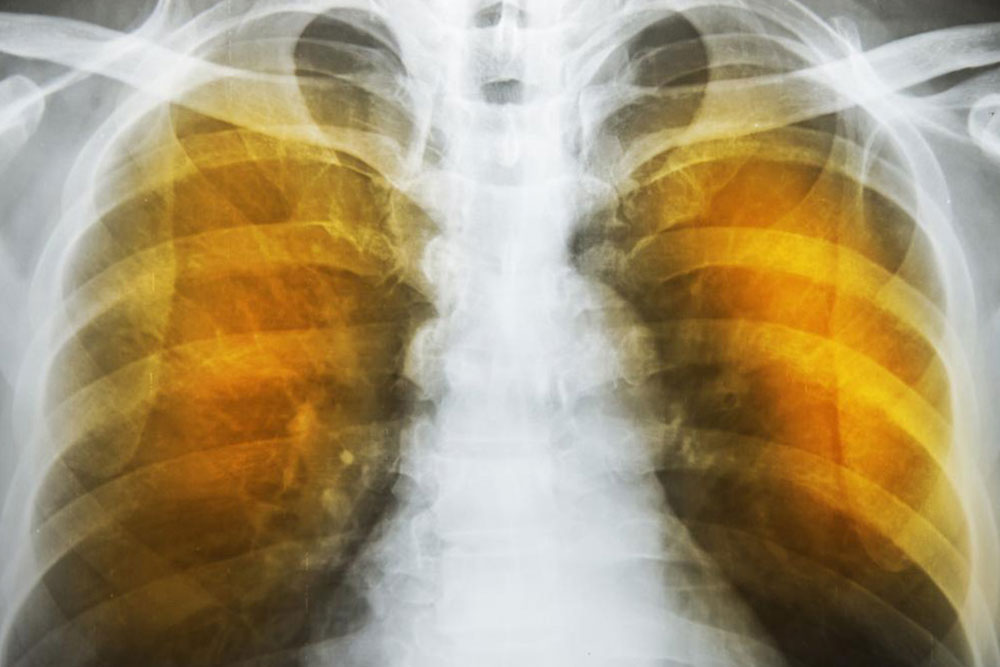

Emphysema is an oppressive respiratory disorder which results from the disintegration of the alveoli, i.e., the tissues where the interchange of gas with blood takes place. Destruction in any large scale will reduce the gas transfer area and the process of gas transfer itself, leading to oxygen starvation or hypoxia.